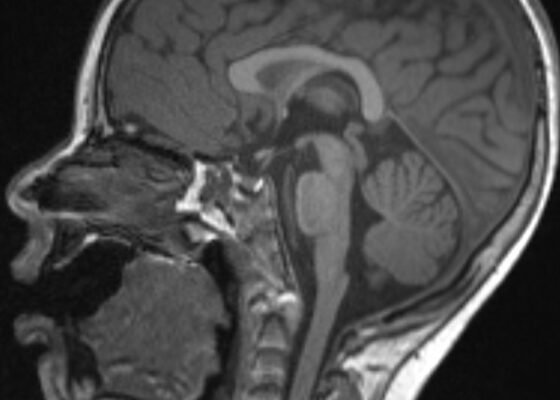

An Unusual Case Report of a Toddler with Metastatic Neuroblastoma Mimicking Myasthenia Gravis

DOI: https://doi.org/10.21980/J8G35VWhile still in the ED, MRI with and without gadolinium contrast of the brain, orbits, and cervical, thoracic and lumbar spine were obtained to evaluate for possible CNS lesions including encephalitis, myelitis, or demyelination. Imaging, however, demonstrated multiple unexpected findings: a T1 hypointense, T2 hyperintense and heterogeneously enhancing right adrenal mass measuring 2.7 x 2.1 x 3 cm (yellow asterisk) along with heterogenous enhancement at the clivus, C6, C7, T7, T8, T12, and L3 vertebral bodies (red asterisks). There were otherwise no significant intracranial signal or structural abnormalities and normal orbits.